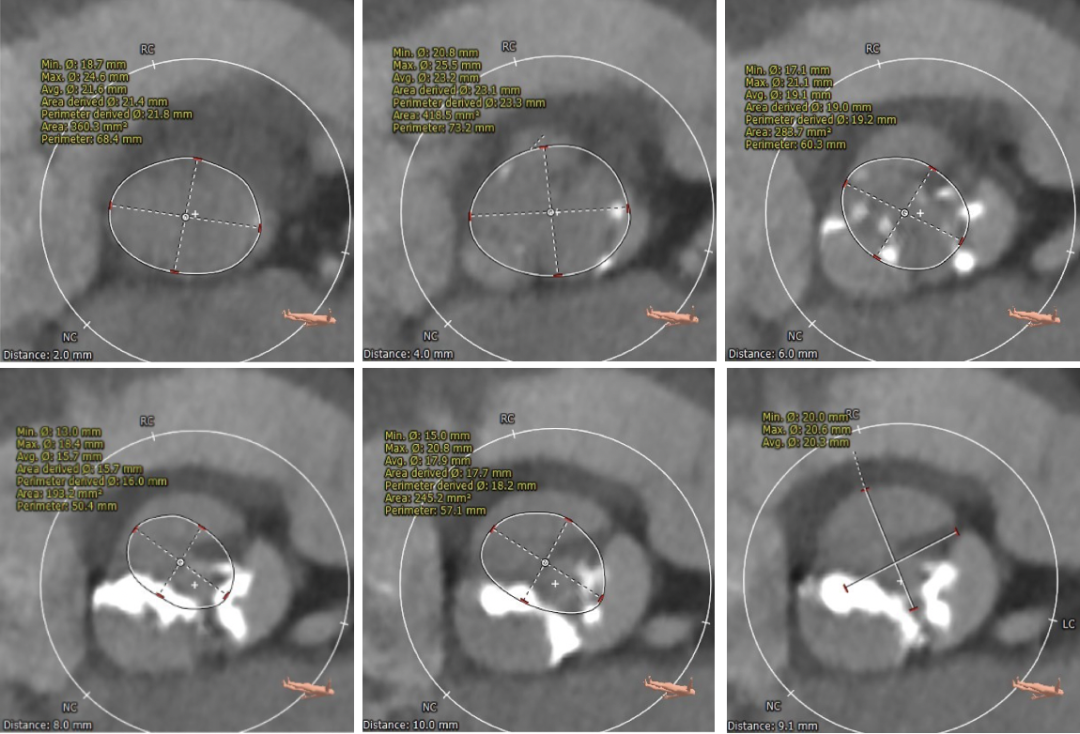

主动脉根部测量

瓣环上多平面测量

经过团队严谨的评估及充分的讨论,使用右侧股动脉为主入路,选定跨瓣和球囊预扩角度为左冠切线位,20mm球囊预扩张。预装载TaurusOne®AV26瓣膜,瓣环下0-2mm偏高位,在左右重合体位下释放。